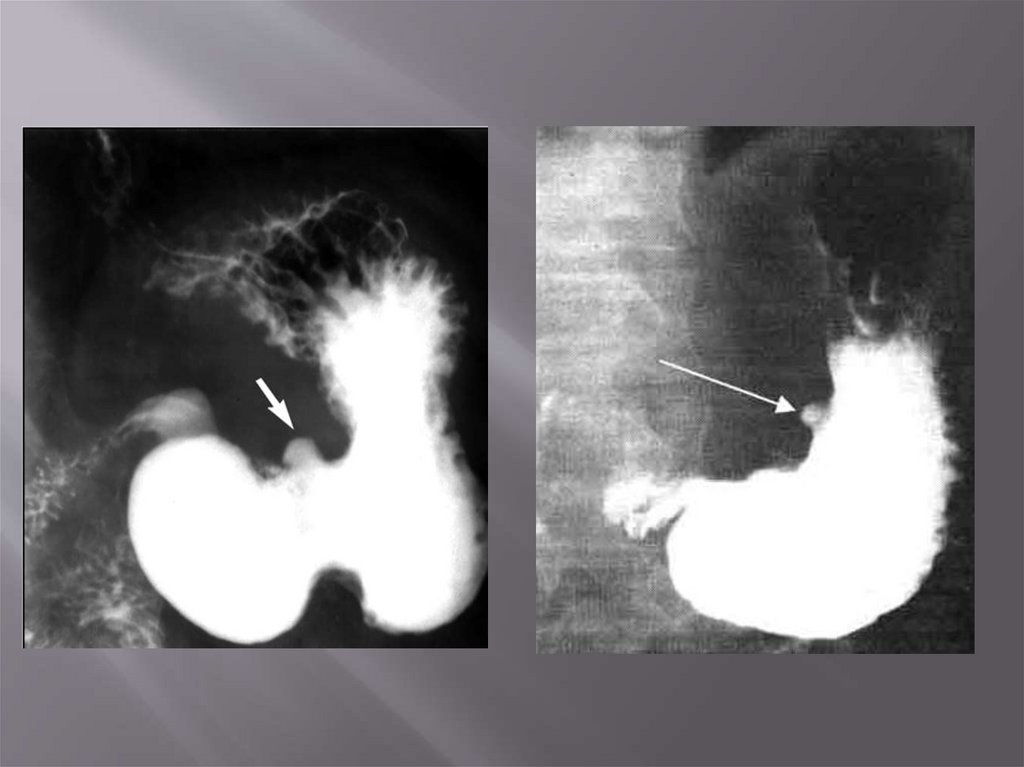

Диагностика

•ОАК

•Кал на скрытую кровь

•ФГДС

•Рентгенография желудка и 12 п.к

•Обзорная рентгенография ОБП, УЗИ ОБП

(наличие свободного газа, выпота в брюшной

полости)